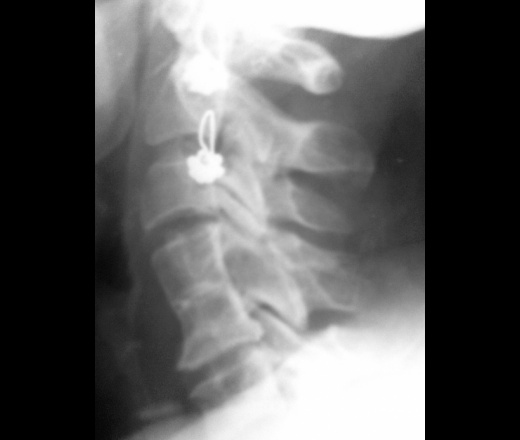

Определяется синостоз тел позвонков, недоразвитый м\п диск между ними, сужение сросшихся позвонков, «талия» между ними, также определяется синостоз одноименных дугоотросчатых суставов. Аномалия Клиппеля-Фейля.

конкресценция C4-C5.Остеохондроз.Сережки.

ну, скажем. конкресценция неполная-диск прослеживается

а чего без прямой? может Клиппеля-Файля?

Клиппеля-Файля